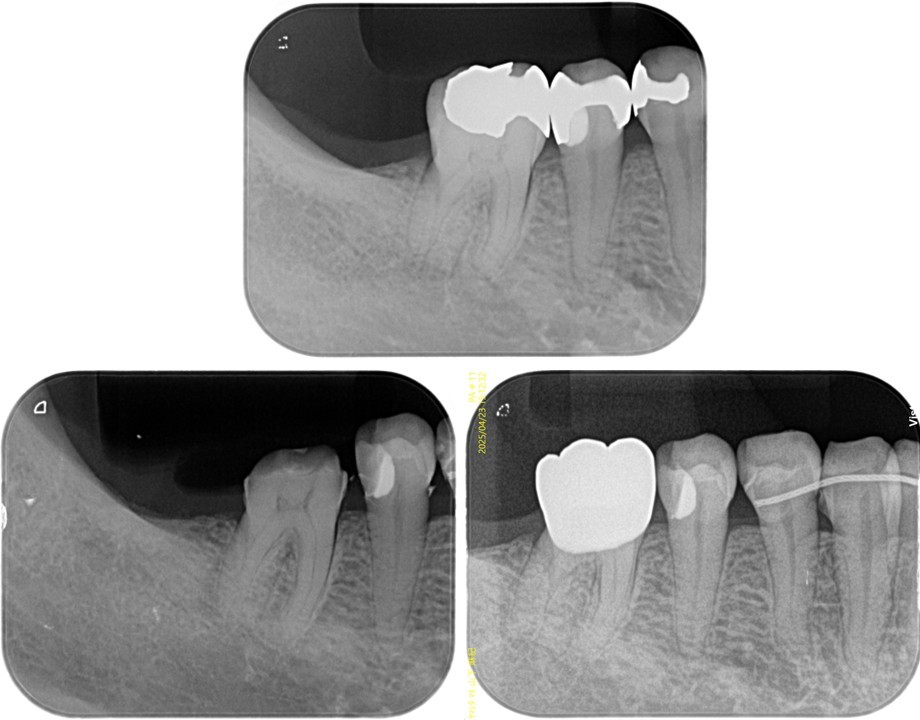

機能的な咀嚼障害を主訴に来院(図18・19)。咬合状態は不安定で、矯正治療を含めた全顎的な治療が必要と診断した。治療計画では右上4・6、左上4・6、左下6部に、それぞれインプラント治療を計画した。右上5、左上5は、隣在歯が近遠ともインプラント治療になるため感覚受容器が乏しくなることが予測されるため、歯髄の有無が大きく影響されやすい環境と判断した。

今回、インプラントを用いた咬合再構成症例を目指したため最終補綴設計は全て単冠処理することを計画し、インプラントが隣接する天然歯の状態は有髄の状態を目指した。右側上下5、左上3・5、左下5は、初診時の段階でう蝕が広範囲で進行していたためVPTを行った。左上4部に行ったインプラントのインテグレーションが不良であったため治療期間中に撤去し、再埋入予定のため左上3・5はプロビジョナル・レストレーションではあるが、VPTを行った5歯は有髄歯の状態で術前の補綴設計通り、単冠処理で治療が遂行している(図20〜26)。今後、万が一再介入の必要性が発生したとしても、今回単冠処理で終了していることで、対応は比較的しやすい状態であると考える。

(図25)治療経過

上4番のインプラント再埋入待ちの補綴装置装着状態

(図26)術後レントゲン像

左上1番以外は天然歯は全て有髄歯の状態で保存できている